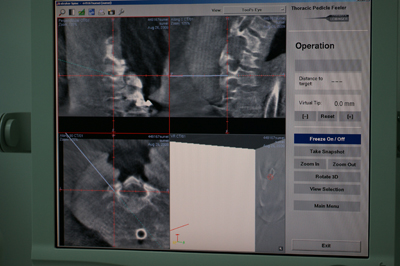

术中导航